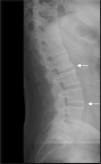

Bone fusions in the cervical spine, calcification of ligaments and syndesmophytes in the lumbar spine were observed through spine radiography (Figure 1), and Grade II (right)/Grade III (left) sacroiliitis was observed through sacroiliac joint radiography. Computed tomography (CT) revealed ankylosis foci at the sacroiliac joint (SI) and bilateral ossification of the iliolumbar ligament (Figure 2B). Similarly, magnetic resonance imaging demonstrated ossification of the iliosacral ligaments in the lower portions of the sacroiliac joints and no significant findings in the upper portions of the SI joint (Figure 2C).

Occasionally, patients with HP may have clinical and radiologic characteristics resembling AS1 due to paravertebral calcification and ossification12. The syndesmophyte in our HP patient, which exhibited the origination in the vertebral margin and preservation of disc space characteristic of AS, led to the misdiagnosis of AS. This finding is distinct from osteoarthritis in which osteophytes are horizontal and there is a significant reduction in disc space.13 The predominant localization in the lumbar region also suggested the diagnosis of AS, although any spinal location may be involved in HP.13 Diffuse idiopathic skeletal hyperostosis (DISH) was unlikely, considering the radiologic spine features, the early appearance of calcifications (before the fourth decade) and the absence of co-morbidities such as dyslipidemia and diabetes mellitus type 2.12